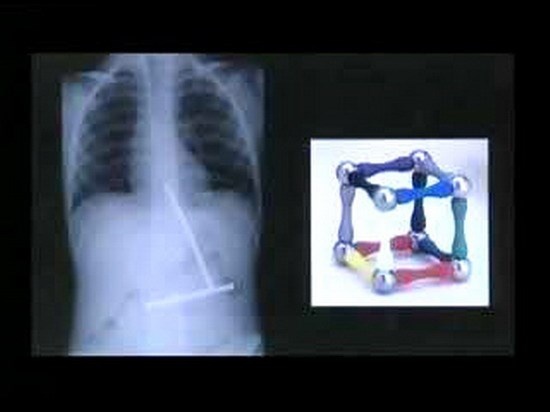

| Phim chụp X-quang này cho thấy cậu bé đã nuốt những thanh nam châm rời nhau của một khối hình. Khi các bác sĩ phẫu thuật thì các thanh nam châm đã ghép lại với nhau. |